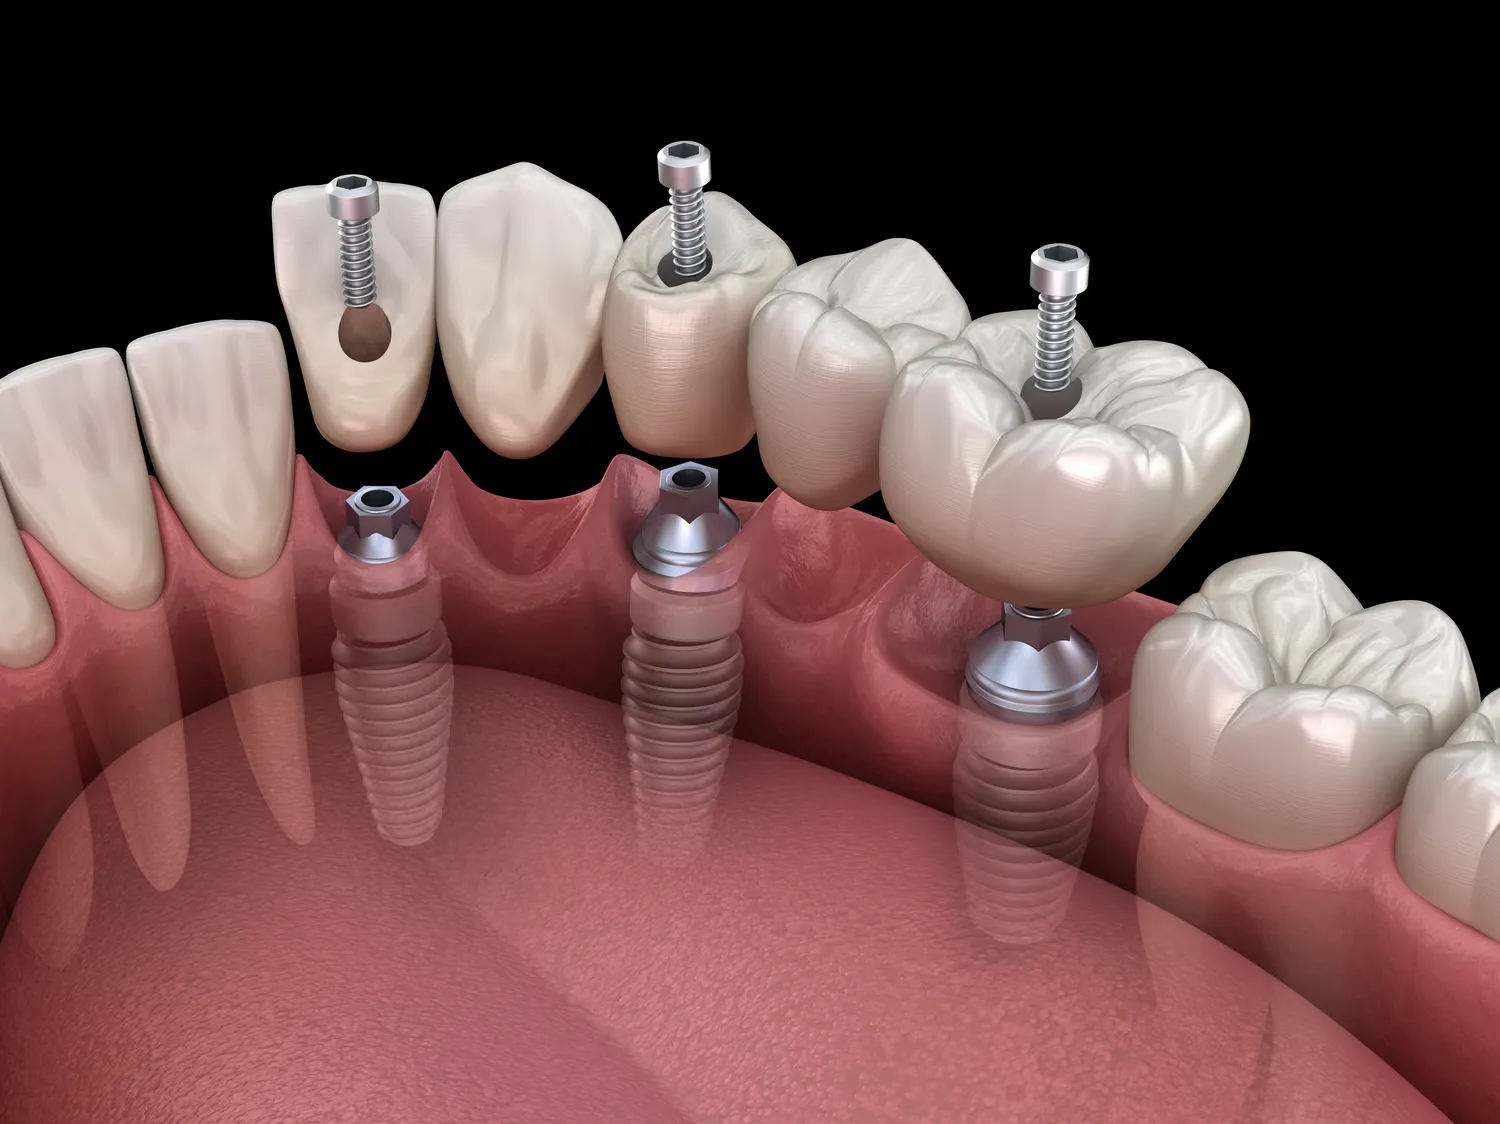

W dzisiejszych czasach stomatologia rozwija się w szybkim tempie, a nowoczesne metody leczenia zębów stają się coraz bardziej dostępne dla pacjentów. W przypadku ubytków próchnicowych coraz częściej stosuje się techniki minimalnie inwazyjne, które pozwalają na oszczędzenie zdrowej tkanki zęba. Przykładem takiej metody jest ozonoterapia, która polega na wykorzystaniu ozonu do dezynfekcji ubytków oraz wspomagania procesu gojenia. W przypadku leczenia kanałowego nowoczesne technologie, takie jak mikroskopy stomatologiczne czy systemy endodontyczne, pozwalają na precyzyjne oczyszczenie kanałów korzeniowych oraz zwiększają skuteczność zabiegu. Dodatkowo zastosowanie materiałów biokompatybilnych do wypełnień kanałów korzeniowych sprawia, że proces gojenia przebiega szybciej i skuteczniej. Coraz większą popularnością cieszą się także implanty dentystyczne jako alternatywa dla utraconych zębów. Dzięki nim pacjenci mogą cieszyć się pełnym uzębieniem oraz poprawić estetykę swojego uśmiechu.